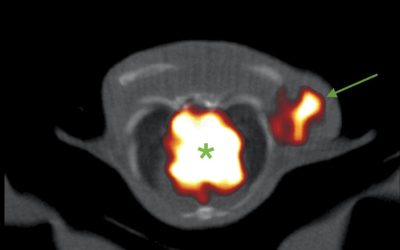

La radiocirugía craneal y extracraneal. Indicación clínica

Mientras el tratamiento sistémico (oral o intravenoso) suele ser la base terapéutica en las pacientes con cáncer de mama metastásico, la radioterapia y de forma específica la radiocirugía craneal y...

La radiocirugía craneal y extracraneal, dos aliadas

¿Alguna vez has imaginado que un rayo atraviesa tu cuerpo de forma casi imperceptible y es capaz de atacar con suma precisión tus metástasis eliminando su actividad e incluso haciéndolas...